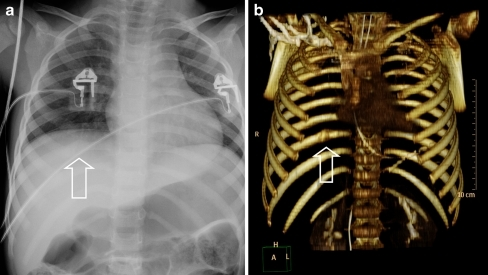

Skeletal survey images in a 9-month-old infant demonstrating multiple fractures at different healing stages consistent with non-accidental injury. The right femur shows an acute spiral fracture. There are healing posterior rib fractures bilaterally. A classic metaphyseal lesion (corner fracture) is visible at the distal tibia. The skull radiograph shows a parietal fracture. These multiple fractures at different stages of healing are highly suspicious for NAI.

Source: Educational Paper: Imaging Child Abuse - The Bare Bones • PMC3258405 • CC-BY